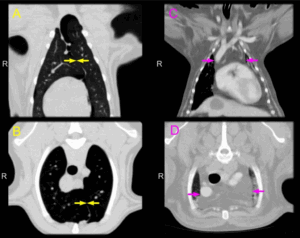

На рисунке (в аксиальной плоскости) полости рта поднижнечелюстное пространство (слева выделено светло-синим цветом) располагается снизу и снаружи от челюстно-подъязычной мышцы. Обратите внимание на основные структуры поднижнечелюстного пространства: поднижнечелюстную железу и лимфоузлы. На аксиальной MPT (Т2) выделено поднижнечелюстное пространство слева. Основными структурами поднижнечелюстного пространства являются поднижнечелюстная железа и лимфоузлы, следовательно, при поражениях этого пространства нужно дифференцировать опухоли железы и заболевания лимфоузлов. На рисунке (корональный срез через полость рта) поднижнечелюстное пространство выделено светло-синим цветом. Поверхностный листок глубокой шейной фасции (желтая линия) покрывает поднижнечелюстное пространство, напоминающее вертикально ориентированную подкову, находящееся снизу и снаружи от челюстно-подъязычной мышцы. В поднижнечелюстном пространстве располагаются переднее брюшко двубрюшной мышцы, поднижнечелюстные лимфоузлы, поднижнечелюстная железа, лицевая вена. Обратите внимание, что поверхностный край поднижнечелюстного пространства образован подкожной мышцей шеи. На корональной MPT (Т1) определяется поднижнечелюстное пространство в виде подковы, распространяющееся с одной стороны на другую, лежащее ниже и наружнее челюстно-лицевой мышцы и глубже подкожной мышцы шеи. Обратите внимание на отсутствие вертикальной фасции или перегородок, что делает возможным беспрепятственное распространение патологических процессов верхнечелюстного пространства через среднюю линию.

На первой и самой верхней из трех аксиальных томограмм (КГс КУ), расположенных сверху вниз, определяется самая верхняя часть поднижнечелюстного пространства. Обратите внимание на хвост околоушной железы в поднижнечелюстном пространстве слева. На более каудальном изображении определяется расширенное поднижнечелюстное пространство, в котором находятся поднижнечелюстная железа, лимфоузлы, лицевая вена. Глубокая часть поднижнечелюстной железы заполняет передний край подъязычного пространства слева. На аксиальной КТ нижних отделов поднижнечелюстного пространства с КУ отмечены все его границы. Обратите внимание, насколько большими становятся поднижнечелюстные железы в нижних отделах. Также заметьте, что переднее брюшко двубрюшной мышцы с обеих сторон заполняет поднижнечелюстное пространство в передних внутренних отделах.